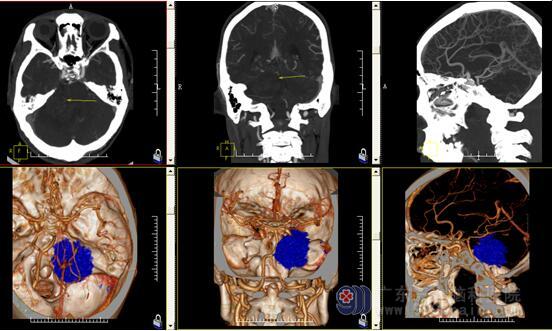

术前CT及脑MRV结果示1.右侧桥小脑角区占位病变,考虑为听神经鞘瘤;2.左侧乙状窦及横窦显示变细,考虑发育变异。

术前CTA检查示右侧桥小脑角区占位性病变内示少许小血管影,邻近右侧大脑后动脉受推挤,相应内听道明显扩大,右侧桥小脑角区占位性病变内存在少许小血管,考虑为听神经鞘瘤可能。